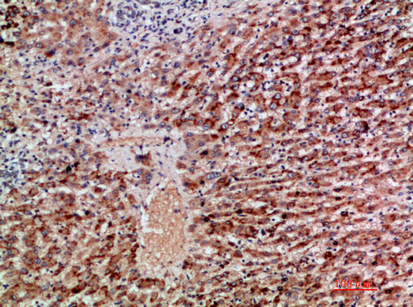

IHC (Immunohiostchemistry)

(Immunohistochemical analysis of paraffin-embedded human-liver-cancer, antibody was diluted at 1:200)